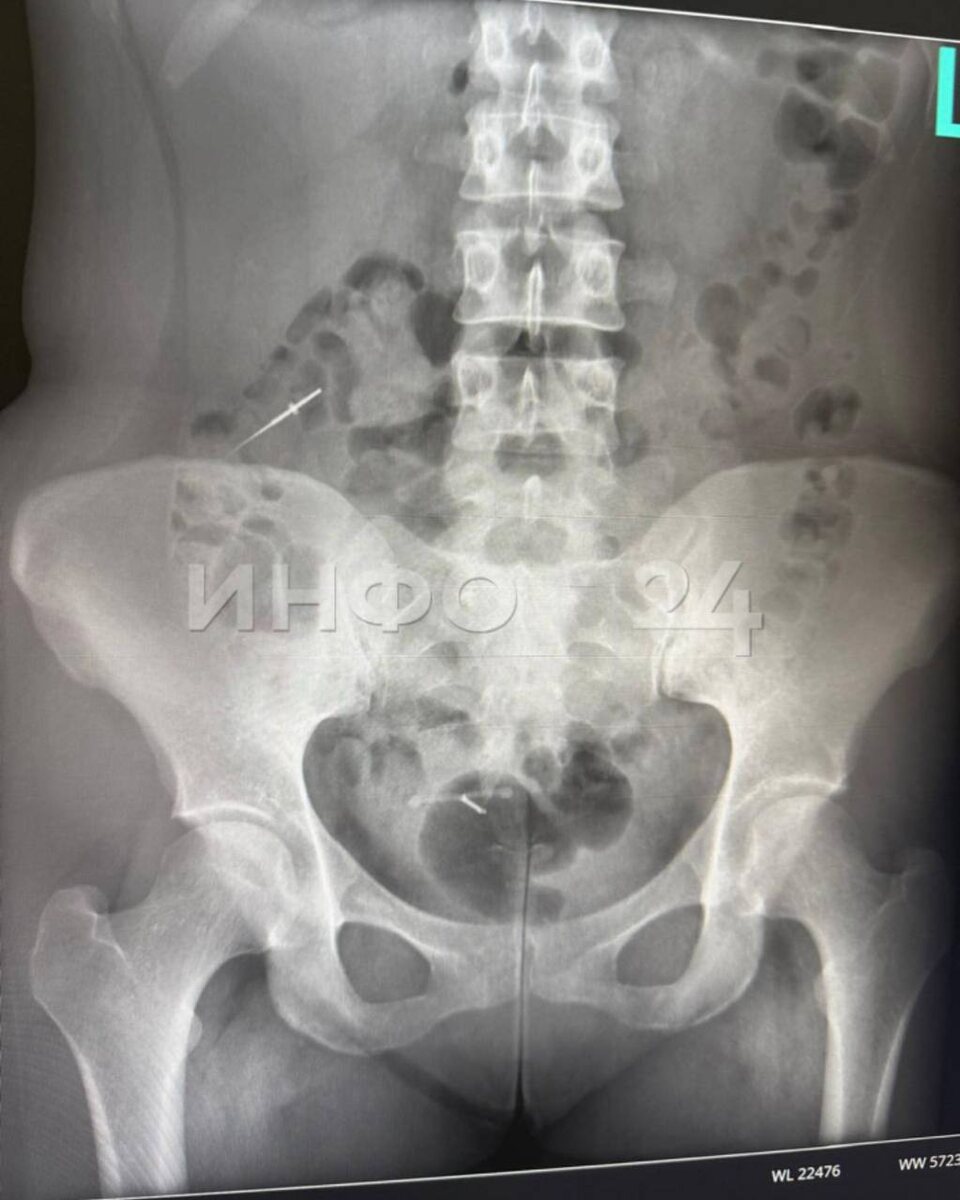

🔵🔵🔵 Стоматолог из Башкирии потерял иглу во рту пациентки. Предмет нашли в кишечнике спустя три дня.

По данным Инфо24, Екатерина поехала лечить зубы в поселок Приютово. По словам девушки, врач почему-то не использовал коффердам (латексную завесу), чтобы исключить попадание в гортань инородных тел. Доктор закончил лечение зуба, и девушка при глотании почувствовала небольшой укол. Екатерина сказала об этом врачу, но тот заявил, что, скорее всего, это был кусочек пломбы. Екатерину все же отправили на УЗИ в стоматологической клинике, там ничего не нашли.

В понедельник она поехала долечивать зуб, попросила пересчитать инструменты, врач сказал, что все на месте. Но у Екатерины начал болеть живот, новый рентген показал, что в кишечнике — игла. Ее положили в больницу. Сейчас врачи ждут, выйдет ли предмет сам или придется делать операцию.